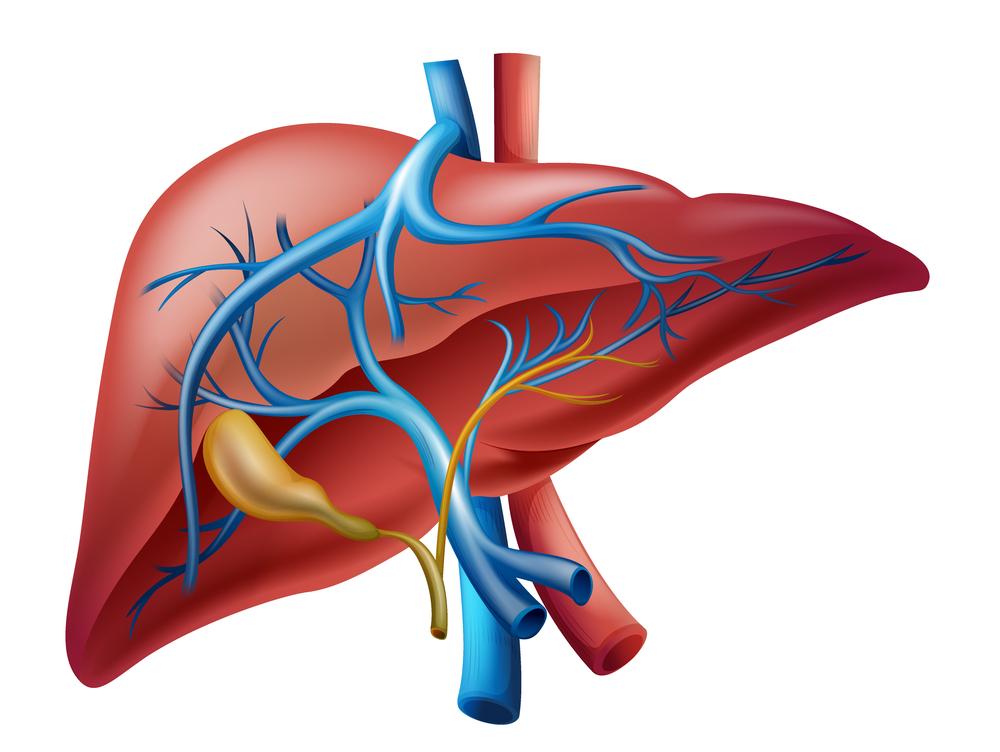

Печень обезвреживает токсические соединения, устраняет избыток гормонов, витаминов, конечных продуктов метаболизма. Обеспечивает белковый обмен, принимает активное участие в иммунологических реакциях, компенсирует кровопотерю в случае серьезных травм.